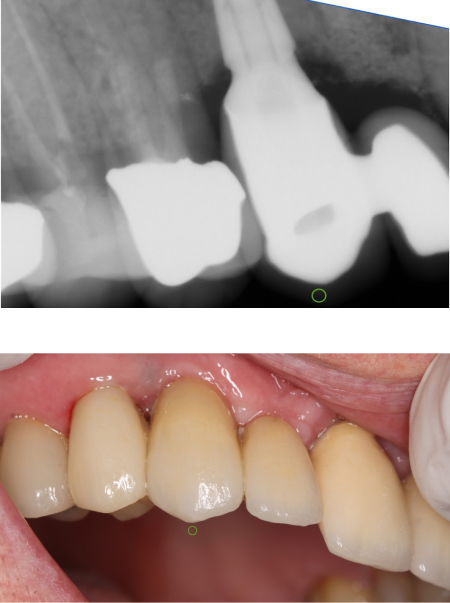

Implant supported teeth

Implant bridge

Single tooth implant